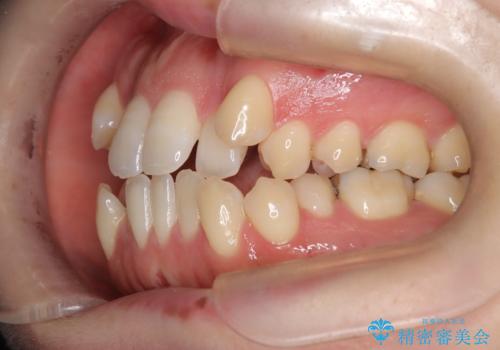

- 前歯のガタガタや八重歯の位置の乱れが気になっていた患者様に対して、ワイヤー矯正を行いました。矯正の過程で、スペースを確保するために上下左右の小臼歯を抜歯し、歯全体のバランスと機能性を考慮しながら理想的な歯列に仕上げました。

抜歯によって確保したスペースを活用し、効率的に歯列を整えました。前歯のガタガタと八重歯が解消され、自然で美しい仕上がりを実現しました。